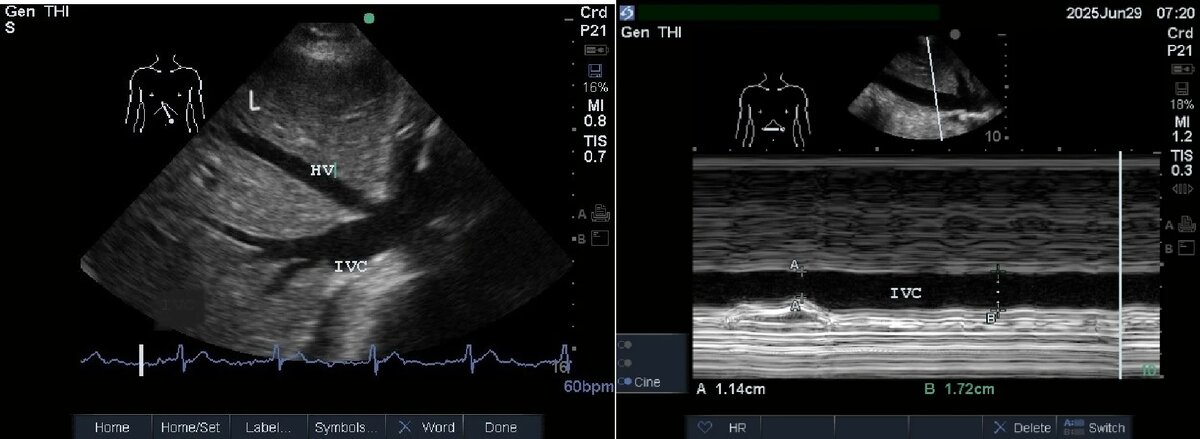

Чтобы оценить изменение диаметра нижней полой вены (НПВ) в течение дыхательного цикла, мы используем индекс коллапса НПВ (IVC collapsibility index, IVCCI). Врач измеряет максимальный (IVCmax) и минимальный (IVCmin) диаметры НПВ на протяжении цикла. IVCCI рассчитывается по формуле (IVCmax - IVCmin) / IVCmax. У пациентов на спонтанном дыхании диаметр НПВ менее 2,1 см с IVCCI более 50% (на вдохе при дыхании через нос) обычно указывает на центральное венозное давление (ЦВД) 0-5 см.вод.ст. Диаметр НПВ менее 2,1 см с IVCCI более 50% (на вдохе при дыхании через нос) обычно указывает на повышенное давление в правом предсердии 10-20 см.вод.ст. IVCCI не валидирован для пациентов на искусственной вентиляции легких с положительным давлением.

Рис. 1. Датчик в проекции эпигастрия. Демонстрируется печень (L) с нижней полой веной (IVC) и левой печеночной веной (HV)